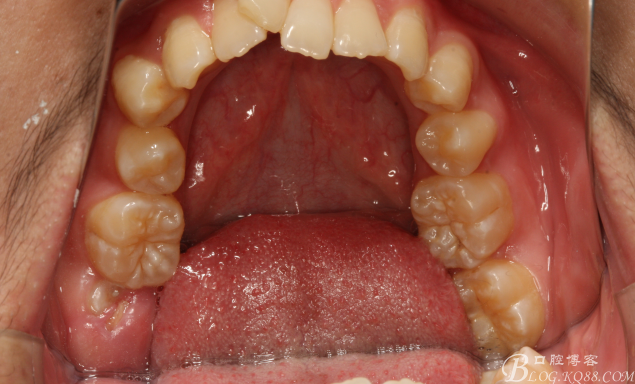

圖4.上腭部影像:腭側(cè)粘膜圓形隆起

圖5.下頜開(kāi)口位影像